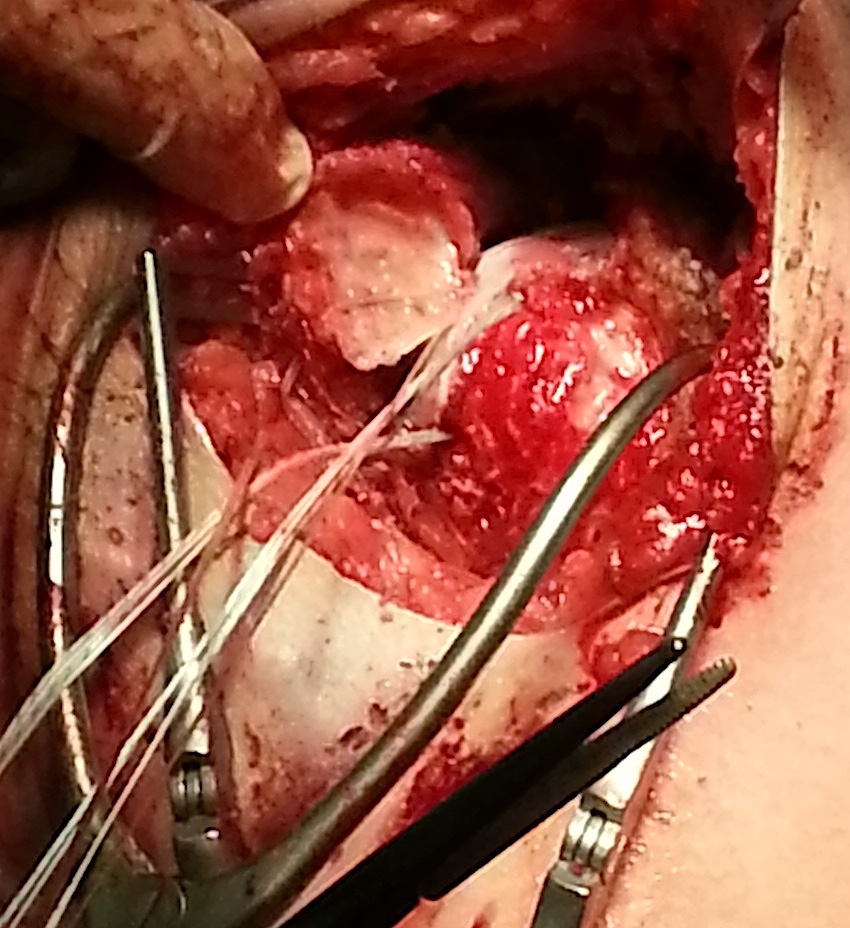

Open versus arthroscopic

Fixation methods

- screw fixation +/- soft tissue washer

- suture anchor + screws

- double row suture anchor fixation

Technique

JSES open fixation lesser tuberosity PDF

Vumedi arthroscopic fixation lesser tuberosity video

Arthroscopy techniques lesser tuberosity avulsion PDF